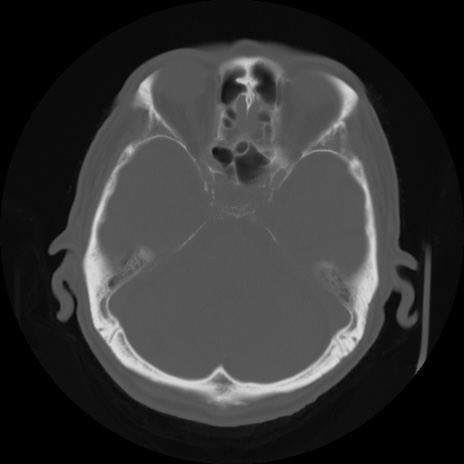

CT(冠状断像)